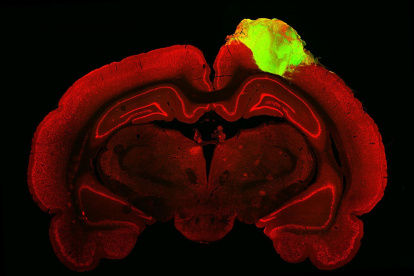

Organoides cerebrales trasplantados a ratas responden a estímulos visuales Agencia EFE, Giannella Espinoza